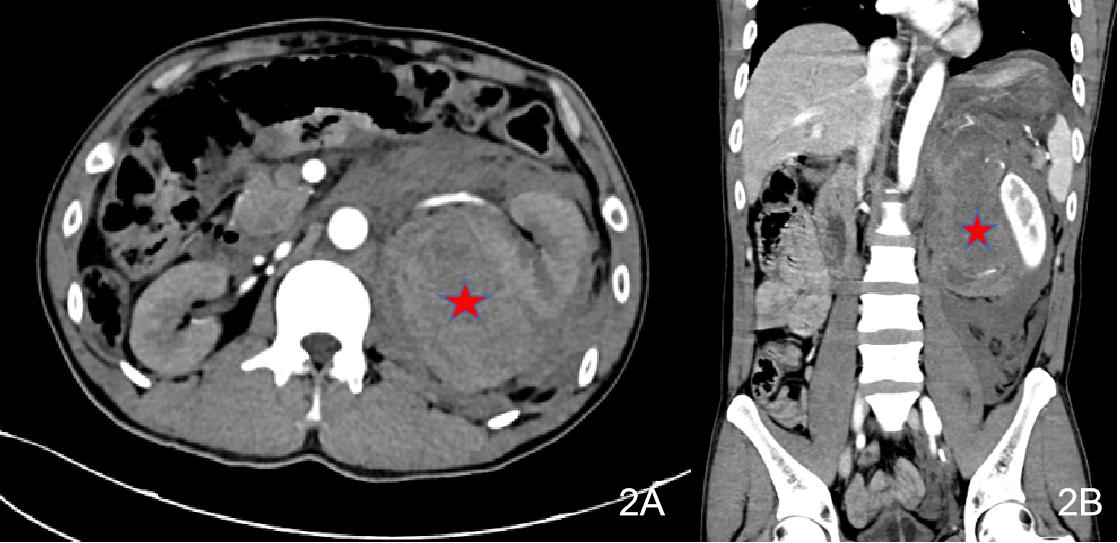

辅助检查如下。2021-06-17本院急诊生化十项:K 3.75 mmol/L,Ca 1.98 mmol/L,CR 116.6 μmol/L,GLUC 30.28 mmol/L;血清肌钙蛋白Ⅰ测定:TnI 21.645 ng/mL;凝血机制六项组合:Fib 1.25 g/L,APTT 21.5 s,DDi 2.97 mg/L;腹部CT平扫+ 增强(见图 2)。左侧肾上腺区占位,考虑肿瘤伴破裂出血,左侧腹膜后、腹盆腔广泛积血,拟左肾上腺来源可能。双下肺渗出,左侧少量胸腔积液,双下肺局部肺不张。右肾小囊肿。2021-06-17常规心电图检查:窦性心动过速非特异性室内传导阻滞T波异常(Ⅰ aVL V5 V6导联低平、浅倒)。

| 图 2 2021-06-17患者2腹部CT(左侧肾上腺占位伴出血) |